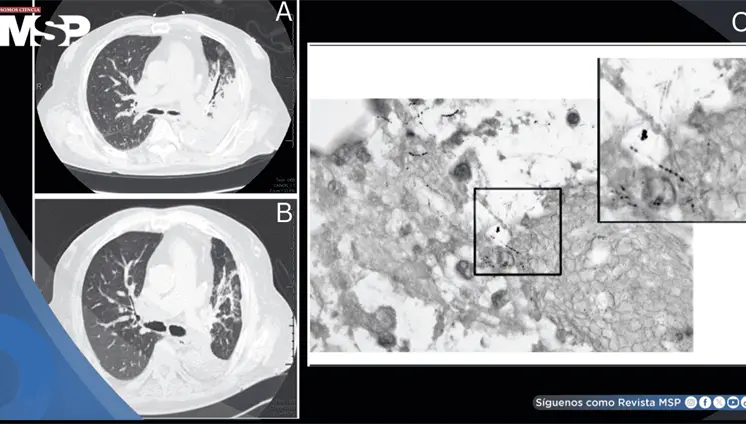

El VIH debilitó gravemente el sistema inmunológico del paciente (CD4 162), permitiendo que una bacteria poco común como Rhodococcus causara un absceso pulmonar severo que simuló tuberculosis y no respondió al tratamiento habitual.